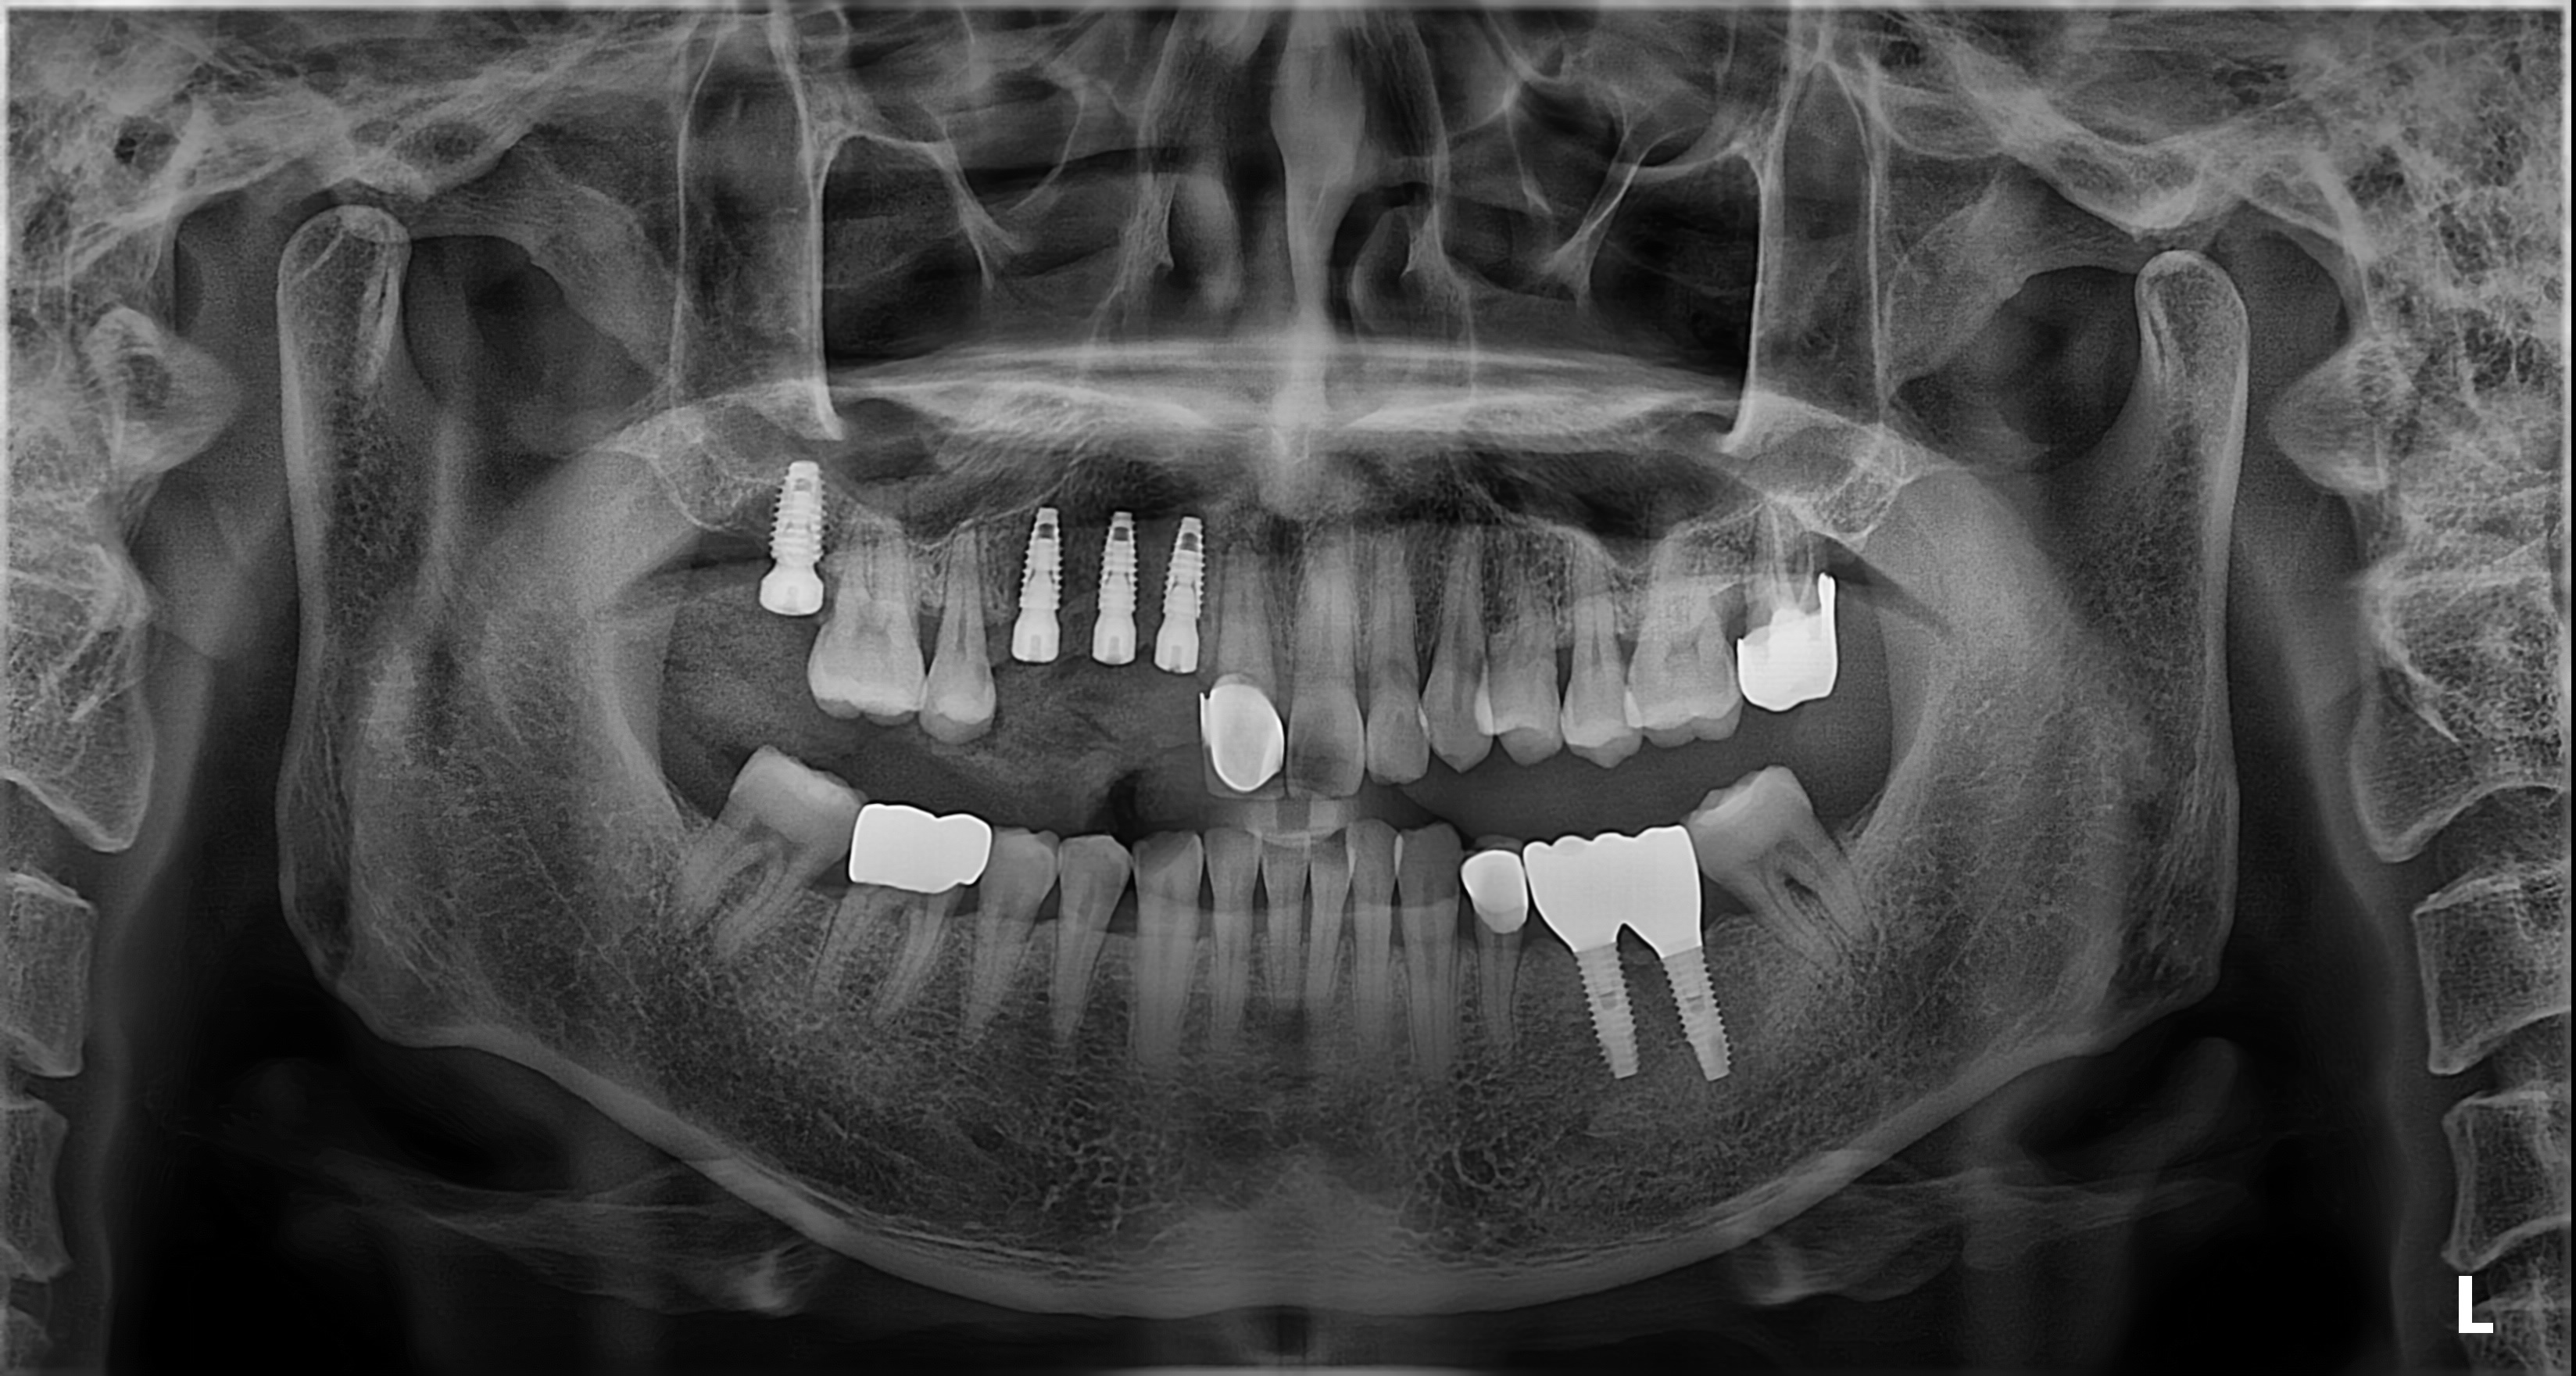

임플란트의 5년 성공율은

최근 발표된 논문들까지 종합해도

90~95% 이상으로 발표되고 있습니다.

매우 높은 성공율입니다.

하지만, 실패한 임플란트를 같은 자리에

재식립했을 때의 성공률은 70%대로 떨어집니다.

(J Oral Maxillofac Surg 78:375-385, 2020)

초기에 발견하고 재식립했을 때는 성공율이 높아집니다.

신뢰가 함께한 진료의 순간

환자 한 분 한 분과 함께 쌓아온 소중한 기록입니다